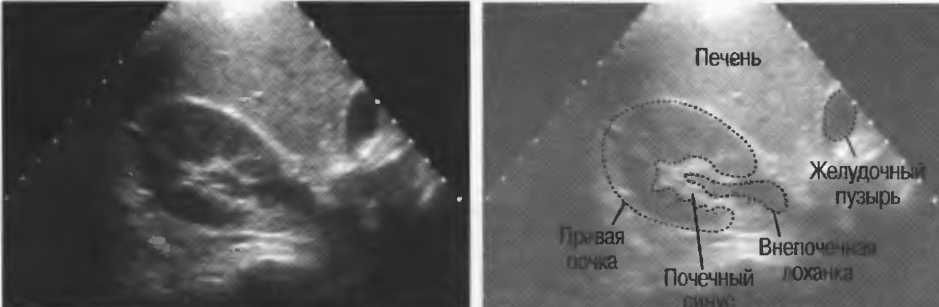

4. У здоровых обследуемых паренхима печени должна быть немного более эхогенна. чем кора рядом расположенной почки (рис. 26).

Рис.26. Продольный срез через печень и правую почку: нормальная паренхима печени более эхогенна, чем паренхима нормальной почки. Это еще один способ проверки качества изображения.